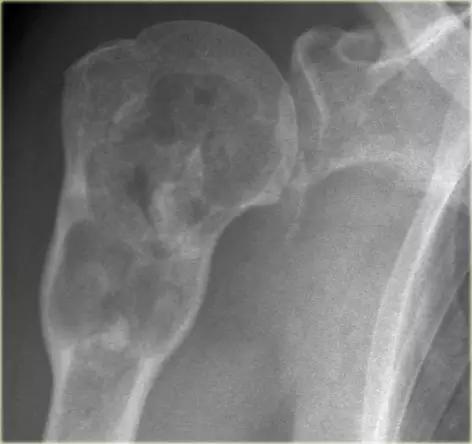

平片显示肱骨骨干的边缘欠清的溶解性病变。注意皮质骨的隧道(红色箭头)。在MR上注意到皮质骨和周围软组织块内的线性异常。鉴别诊断(取决于年龄):尤因氏肉瘤,骨髓炎和骨淋巴瘤。活检显示非霍奇金淋巴瘤